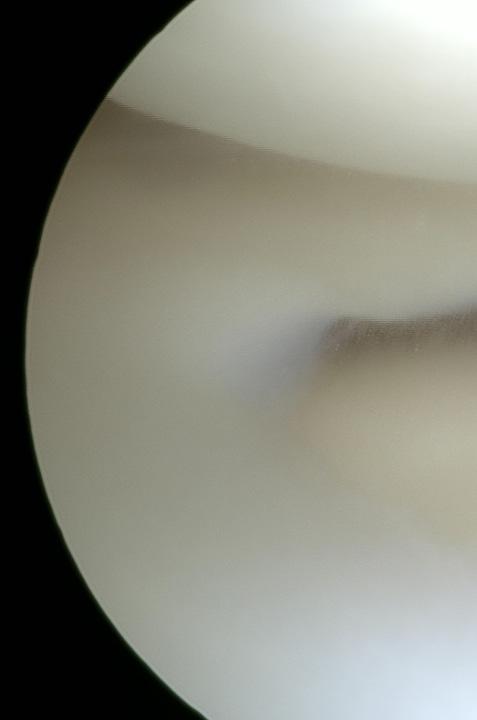

De först kända artroskopiförsöken utfördes för nästan exakt hundra år sedan samtidigt i Japan, av Professor Kenji Takagi, och i Schweiz, av Dr Eugen Bircher.

Ibörjan användes kvävgas för att “blåsa upp” leden. Ytterligare ett antal kirurger beskrev hur endoskopi av en led skulle kunna fungera för att ställa diagnoser in i knäleden. Andra världskriget bromsade tyvärr vidareutvecklingen av artroskopitekniken och den blev lite bortglömd en period. Men Dr. Masaki Watanabe, en elev till nämnda professor Takagi, trodde på sin handledarens ursprungliga idé och satsade under 50-talet på att rita och bygga ett flertal artroskop. Watanabe-artroskop nummer 21 var det första skopet som verkligen fungerade kliniskt och den första meniskresektion kunde utföras framgångsrikt 1962.

Ejnars föreläsningar var eftertraktade. Han var både en karismatisk talare och dessutom kunde han med sin visuella teknik visa stora färgfilmer och bilder från insidan av ett knä. Detta marknadsförde den artroskopiska tekniken och den fick stort genomslag. Ejnar köpte till och med ett begagnat klippbord för att kunna klippa och redigera sina egna filmer. Han tror att den visuella presentationen ihop med hans begåvning för muntlig framställan och språkkunskaperna bidragit starkt till hans framgångar.